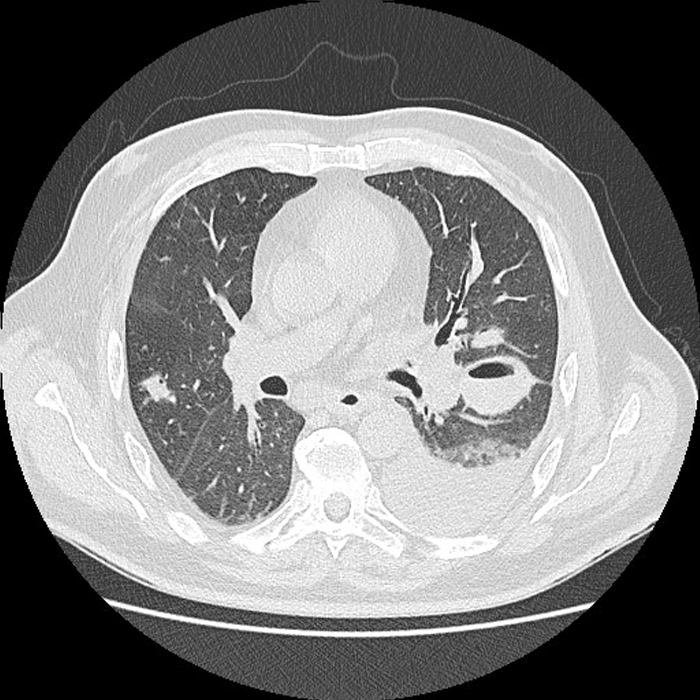

Alla luce di quanto evidenziato dalla radiografia del torace, veniva richiesta un’indagine di secondo livello con una TC del torace con mezzo di contrasto iodato che confermava la presenza di plurime alterazioni focali polmonari escavate con livelli idroaerei, di cui la maggiore di 45 mm al lobo inferiore sinistro, di significato ascessuale. In concomitanza si rilevavano tromboembolie polmonari che interessavano le diramazioni principali a cavaliere per i lobi superiori e i rami segmentari dei lobi inferiori e medio (Figura 1).

Figura 1. Sezione trasversale della tomografia computerizzata del torace con mezzo di contrasto effettuata al momento del ricovero che mostra una evidente lesione escavata al lobo inferiore sinistro di 45 mm con livello idroaereo riferibile a raccolta ascessuale. Concomita versamento pleurico omolaterale in sede antideclive in fase di organizzazione. Un’altra formazione più piccola si visualizza in questa scansione al lobo inferiore destro